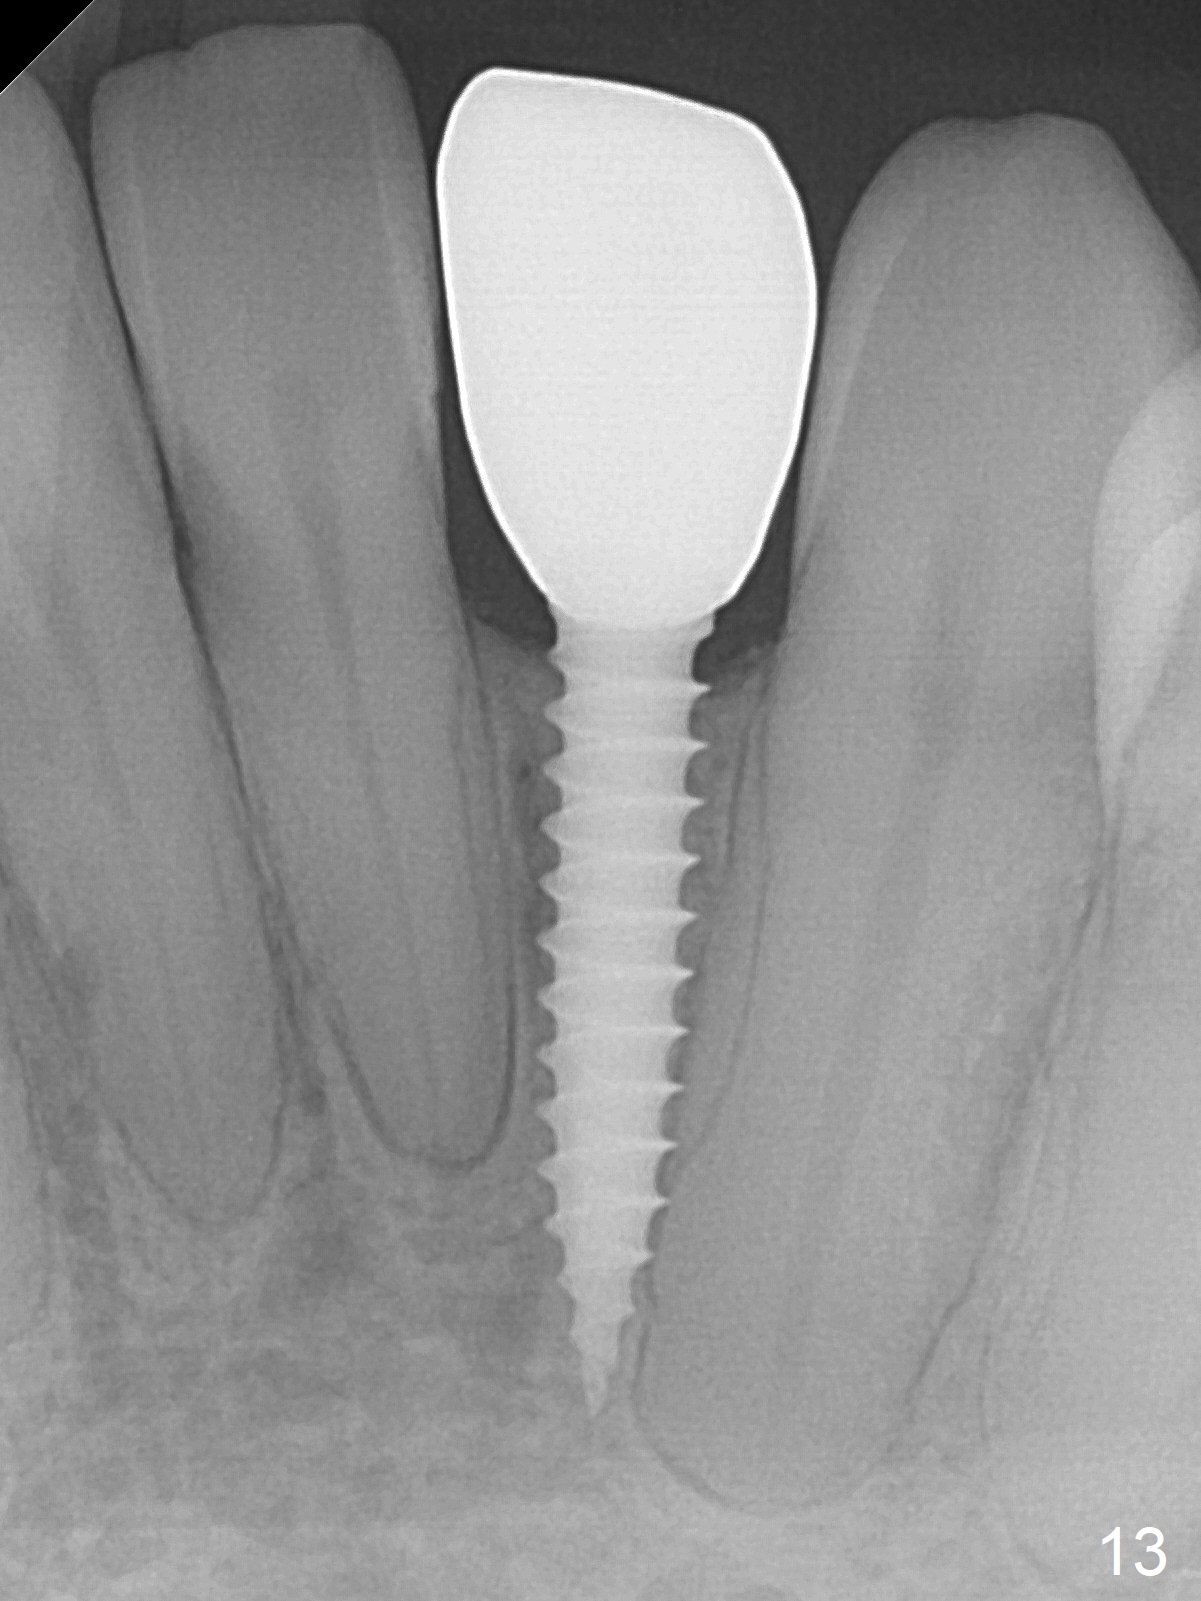

Fig.10: A2 shade guide.  The patient requests A1 for the incisal edge and body and A2.5 for the cervical region.  Fig.11 is taken 22 months post 2nd cementation (4 years postop).  The implant crown remains normal 1 year 10 months post 2nd cementation (4 years 10 months postop, Fig.12,13).